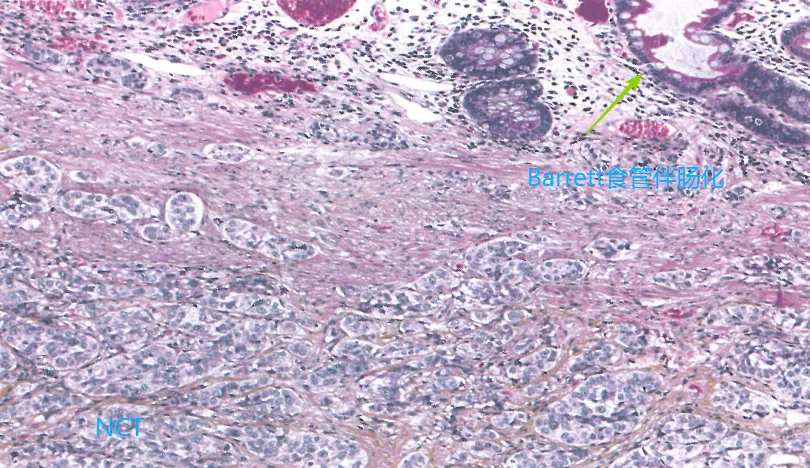

尚不明确,下食管黏膜下腺或Barrett食管中存在内分泌细胞。

三、MiNENs:

通常由低分化神经内分泌癌(NEC)与鳞状细胞癌/腺癌组成